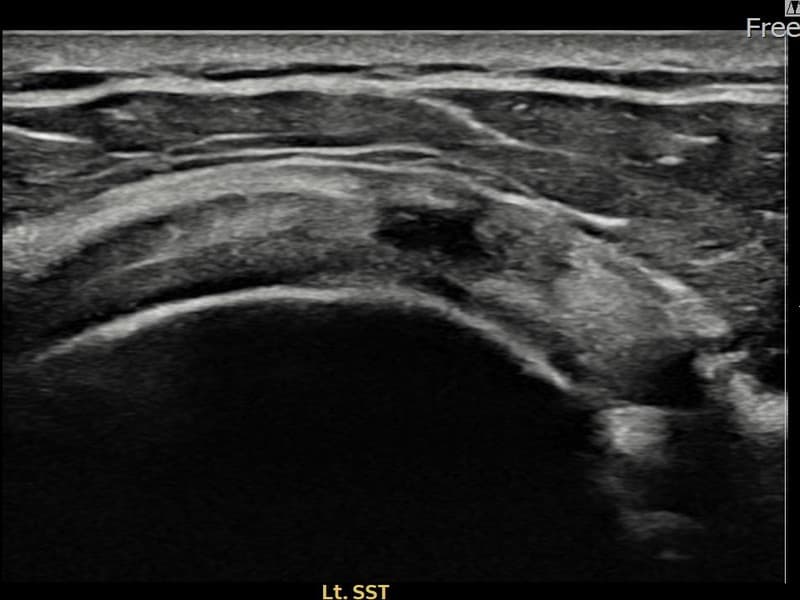

Before

시술 전 초음파 측정 결과 파열 크기는 8mm × 3mm (힘줄 두께의 약 33% 결손)로 확인되었습니다. 시술 전 초음파에서 좌측 극상근건 관절면측의 에코 단절과 힘줄 내 저에코 결손이 확인되었습니다. 시술 후 초음파에서 파열 부위가 재생 조직으로 채워지고 힘줄 에코 패턴이 정상화된 것이 관찰되었습니다.

60대 중반 남성 환자분으로, 왼쪽 어깨 통증이 수개월간 지속되다가 최근 야간 통증까지 생겨 내원하셨습니다. 활동적인 생활을 즐기시는 분으로 통증으로 인해 운동이나 취미 활동에 제약이 생기셔서 비수술 치료를 강력히 원하셨습니다. 초음파 검사에서 좌측 극상근건 관절면측 부분파열이 확인되었으며, 초음파 유도 하 축소봉합술을 시행하였습니다. 시술 후 단계적으로 재활 운동을 진행하였고, 10주 후 추적 초음파에서 파열 부위가 재생 조직으로 채워지고 힘줄 연속성이 회복되어 정상 생활에 복귀하셨습니다.